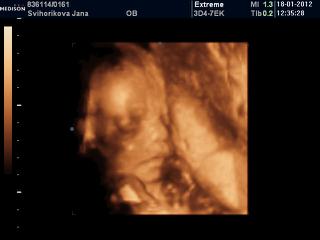

Ahojte babulky, tak sjme doma z utz..mala je nadherna, sice stale mensi, dneska jsme 27+1, ale zodpovidame na na 25+6, ale to uz od zacatku vime...jen zla poloha☹stale chudak je zkroucena v 1/4 bricha, je to tim, ze mam dvourohou delohu a mala se tam nevejde☹z 90% se z teto polohy nedokaze sama vykloubit a na radu prichazi sekcie☹

CD mam plne fotek, ale ne moc kvalita, jak vuci mista v maternici, tak tim ze je mala natlacena a neni misto, kde by se dalo na ni podivat...pry se k nim mam objednat jeste na morfologicky v 30tt a ze kdyz to bude lepsi, tak mi na to CD doplni dalsi fotky gratis, no fakt mila baba, hrozne prijemna, necelou hodinu s enam venovala aza ty penize to fakt stoji...

Na prvni fotce je krasne videt, jak ma oblicejik, rucicku a jeste aj nozicka, chudak je fakt v ulite, nema tam misto, snad to nebudou do budocich tydnu komplikace